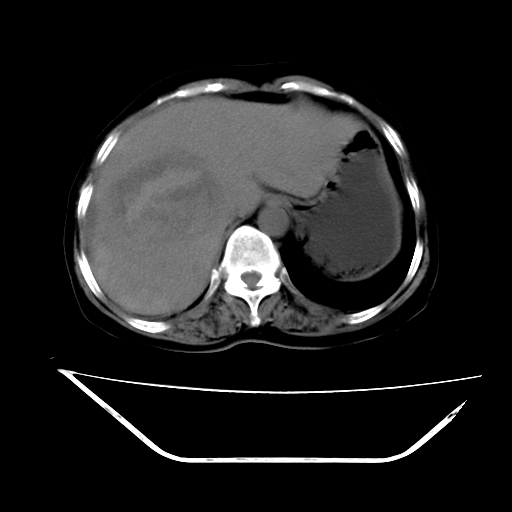

标题: CT16642:男62岁,突发性上腹部疼痛来诊。请讨论!

2008-6-10ct平扫

6月片:肝血管瘤并破裂出血?肝左外叶囊肿

考虑为肝血管瘤破裂出血并肝包膜下血肿;右侧少量胸腔积液。

6月份ct片显示肝内巨大混杂密度团块,伴包膜下积液(内含液液平面),增强多无明显强化。只能考虑肝占位病变,并肝内、血膜下血肿。肝ca并出血多见,而肝血管瘤并破裂出血少见。